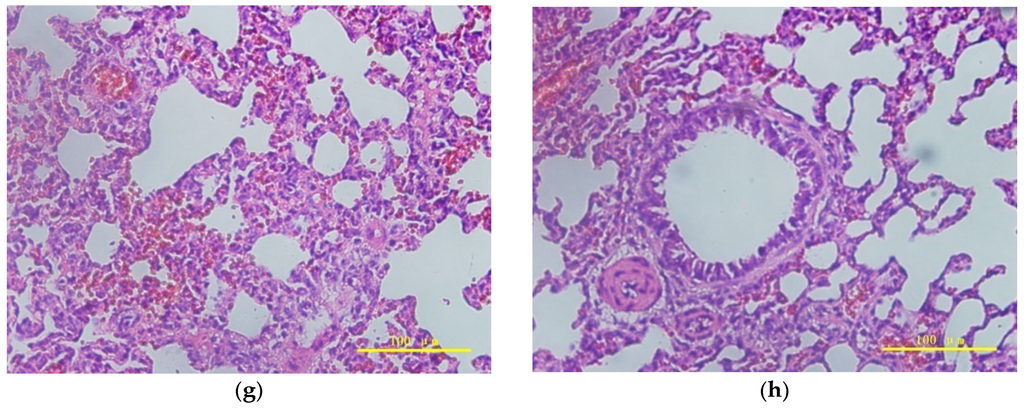

2.4. Pulmonary Toxicity Assessment

3.2.8. Pulmonary Toxicity Assessment